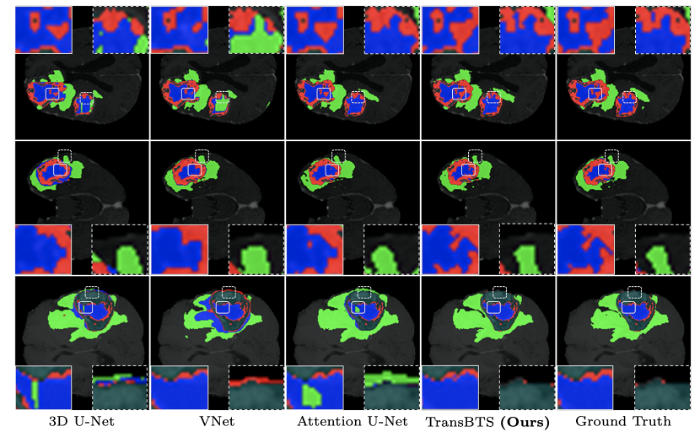

在定性分析方面, 论文展示了多种方法(如3D U-Net、V-Net和TransBTS)在脑肿瘤分割结果上的视觉对比. 通过图3-9的数据可以看出, TransBTS能够更加精准地描述脑肿瘤, 并利用长距离依赖关系建模以更为显著的效果生成精确分割掩膜.

图3-9 基于Transformer的多模态脑肿瘤分割